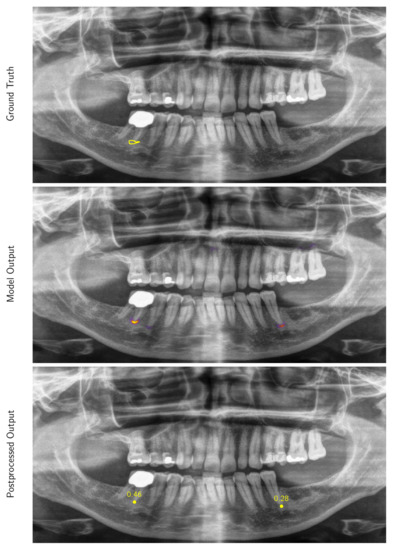

3.2. Performance of the Deep Learning Algorithm